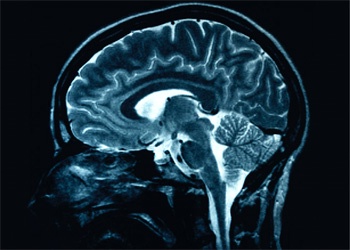

Scientists have revealed the role of one type of brain cell in the development of a process crucial for memory and learning.

An international study involving the University of Aberdeen has found that these brain cells - known as basket cells - continue to develop after birth, forming strongly wired networks.

Basket cells control where and when information flows in the brain by acting in what is known as an 'inhibitory" way.  Although they make up less than 10% of the nerve cell population in the brain, basket cells efficiently control the activity of the other 90% of our brain cells which behave in an excitatory way.

Researchers found that basket cell networks continue to develop their functional capabilities which help generate the fast rhythms in the brain necessary for learning and memory.

Understanding more about the development of basket cells could give more of an insight into schizophrenia as it has been shown that people with this disease show a reduction in the number of these cells and a reduced wiring among them.